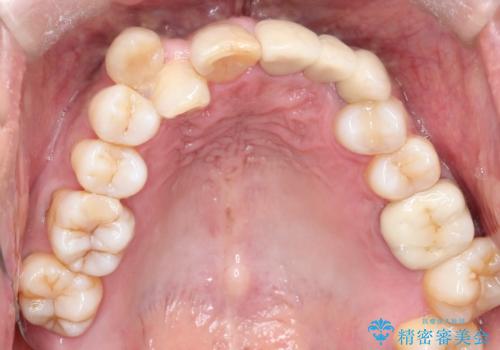

- 50代の患者様で、右上の八重歯と歯並びの乱れを気にされてご来院されました。特に、すでに装着されている前歯のセラミックブリッジを外したくないという強いご希望がありました。精密な検査の結果、八重歯を治すためのスペースが不足しているため、右上の4番目の歯(小臼歯)を抜歯し、そのスペースを利用して歯並び全体を整える治療計画を立案。装置には目立たないインビザラインを採用し、ブリッジを温存しながら八重歯の改善を目指しました。

今回の治療で最も重要だったのは、患者様のご要望通り既存のセラミックブリッジを外さずに矯正を進める点でした。計画通り右上の小臼歯を抜歯し、透明なインビザラインを使用して抜歯スペースを閉じながら、八重歯を正しい位置へ移動させました。ブリッジの形態と調和するに、他の歯の移動を工夫をすることで、複雑な条件をクリア。治療の結果、長年気にされていた八重歯が解消され、見た目が大きく改善しました。50代からでも、ご自身の要望を叶えながら、美しく機能的な歯並びを獲得していただけました。